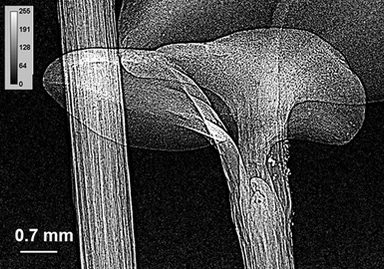

Существуют два типа рентгеновских микроскопов — отражательные и проекционные. В отражательных микроскопах используется явление преломления рентгеновских лучей при скользящем падении. Проекционные микроскопы используют высокую проникающую способность рентгеновских лучей. В них изучаемый объект помещается перед источником излучения и просвечивается рентгеновскими лучами. Благодаря тому, что коэффициент поглощения рентгеновских лучей зависит от размеров атомов, через которые они проходят, такой метод позволяет получать информацию не только о структуре, но и о химическом составе изучаемого объекта.

Проекционные рентгеновские микроскопы представляют собой камеру, в противоположных концах которой располагаются источник излучения и регистрирующее устройство. Для получения чёткого изображения необходимо, чтобы угловая апертура источника была как можно меньше.

Проекционные микроскопы получили широкое применение в различных сферах науки, включая медицину, минералогию, металловедение.

- получить микрорентгенографии биологических и ботанических срезов толщиной до 200 мкм.